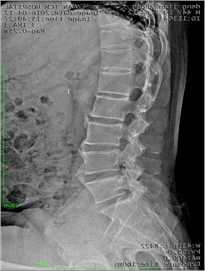

强直性脊柱炎影响表现: